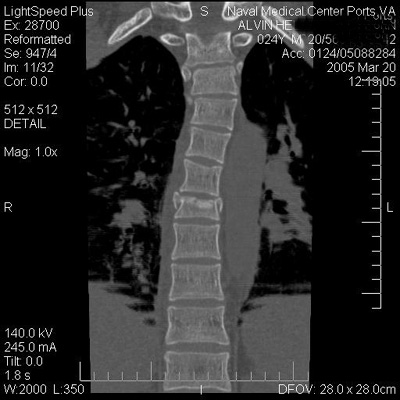

Yes I did. I had a burst fracture to my T8 vertebra-And yup I'm almost 100% healed up-average heal time for a burst fracture is 6-8 weeks--I'm a bit sore right now-but I dont feel it when I ride. I made a decision to get back on my bike today because I love stunting and I'll have to be dead before I quit riding. Here's an X-ray of my spine:

Didn't you post a thread about breaking your back about a month ago? You are healed up already?Yes I did. I had a burst fracture to my T8 vertebra-And yup I'm almost 100% healed up-average heal time for a burst fracture is 6-8 weeks--I'm a bit sore right now-but I dont feel it when I ride. I made a decision to get back on my bike today because I love stunting and I'll have to be dead before I quit riding. Here's an X-ray of my spine: